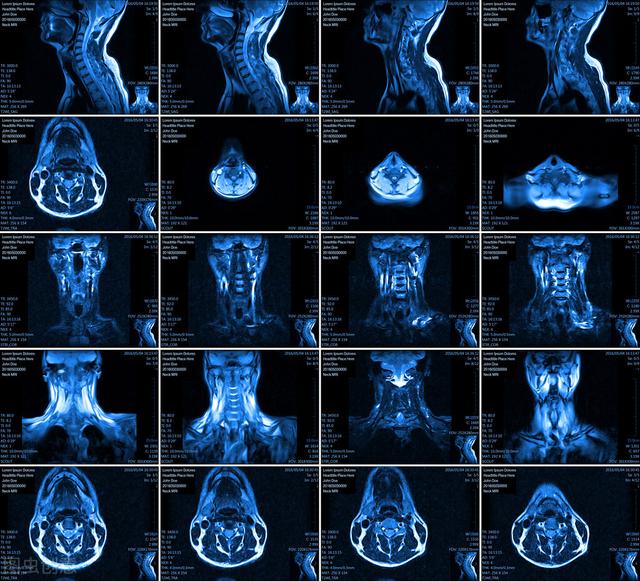

- CT-Le scanner a une meilleure résolution et peut déterminer la taille des vertèbres cervicales et du canal rachidien, la localisation et la taille de la prolifération du cône, le degré de dégénérescence des articulations intervertébrales, la taille du foramen transverse, le degré d'ossification du ligament longitudinal postérieur, la hernie des disques intervertébraux, etc. Le scanner a une meilleure imagerie des tissus osseux et peut visualiser les changements osseux localisés et de petite taille.

- MR-Connu également sous le nom d'examen par résonance magnétique, il peut refléter principalement les tissus mous, les muscles, la moelle épinière, les nerfs et les vaisseaux sanguins environnants, et peut montrer les lésions plus clairement, déterminer la nature des lésions et détecter des lésions relativement petites.